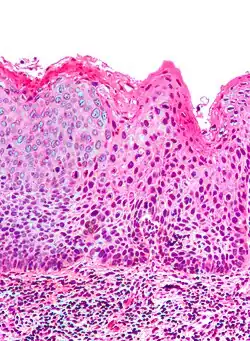

| Micrograph of (classic) vulvar intraepithelial neoplasia III. H&E stain. | |

Classic vulvar intraepithelial neoplasia: associated with developing into the warty and basaloid type carcinoma. This is associated with carcinogenic genotypes of HPV and/or HPV persistence factors such as cigarette smoking or immunocompromised states.

Micrograph of vulvar intraepithelial neoplasia III. H&E stain. -